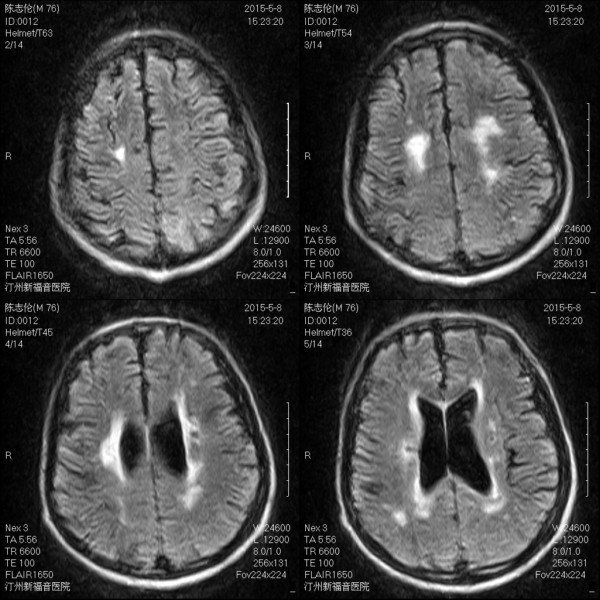

MRI6648:请各位专家帮忙看看 陈旧脑梗病史 有无新发 ...

MRI6648:请各位专家帮忙看看 陈旧脑梗病史 有无新发

不好意思,低场的,没法做dw1

dwi 可能梗死灶周围有出血

增加DWI图像,可以进一步鉴别是否为新鲜梗塞

两侧基底节区多发性腔梗,部分陈旧,脑白质疏松。

新旧兼有

1、有陈旧脑梗,也有新发脑梗。

2、 脑白质疏松。

没有dwi怎么有效判断啊